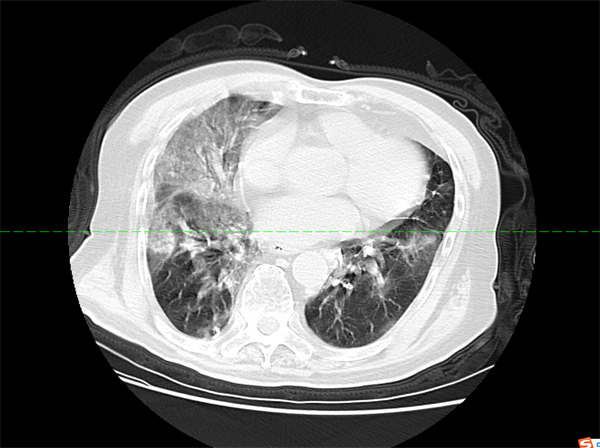

2022年12月26日,患者黄某某,因呼吸困难入院,CT显示:双肺散在多发感染。

同时存在肺气肿、严重低蛋白血症等多种严重病症危及患者生命安全。内四病区主管医生高钰荣立即给予吸氧纠正低氧,抗感染,解痉平喘,化痰止咳,补充白蛋白营养支持等治疗,治疗过程中,患者病情几经反复,甚至感觉希望渺茫,主管医生多次组织科内会诊、讨论,为其制定了科学合理的治疗方案,西医吸氧纠正呼吸衰竭、补充白蛋白营养支持,抗感染,解痉平喘,化痰止咳,配合使用中药,清肺排毒,健脾化湿。经过中西医结合治疗及精心护理,患者病情逐渐稳定,最后顺利出院。